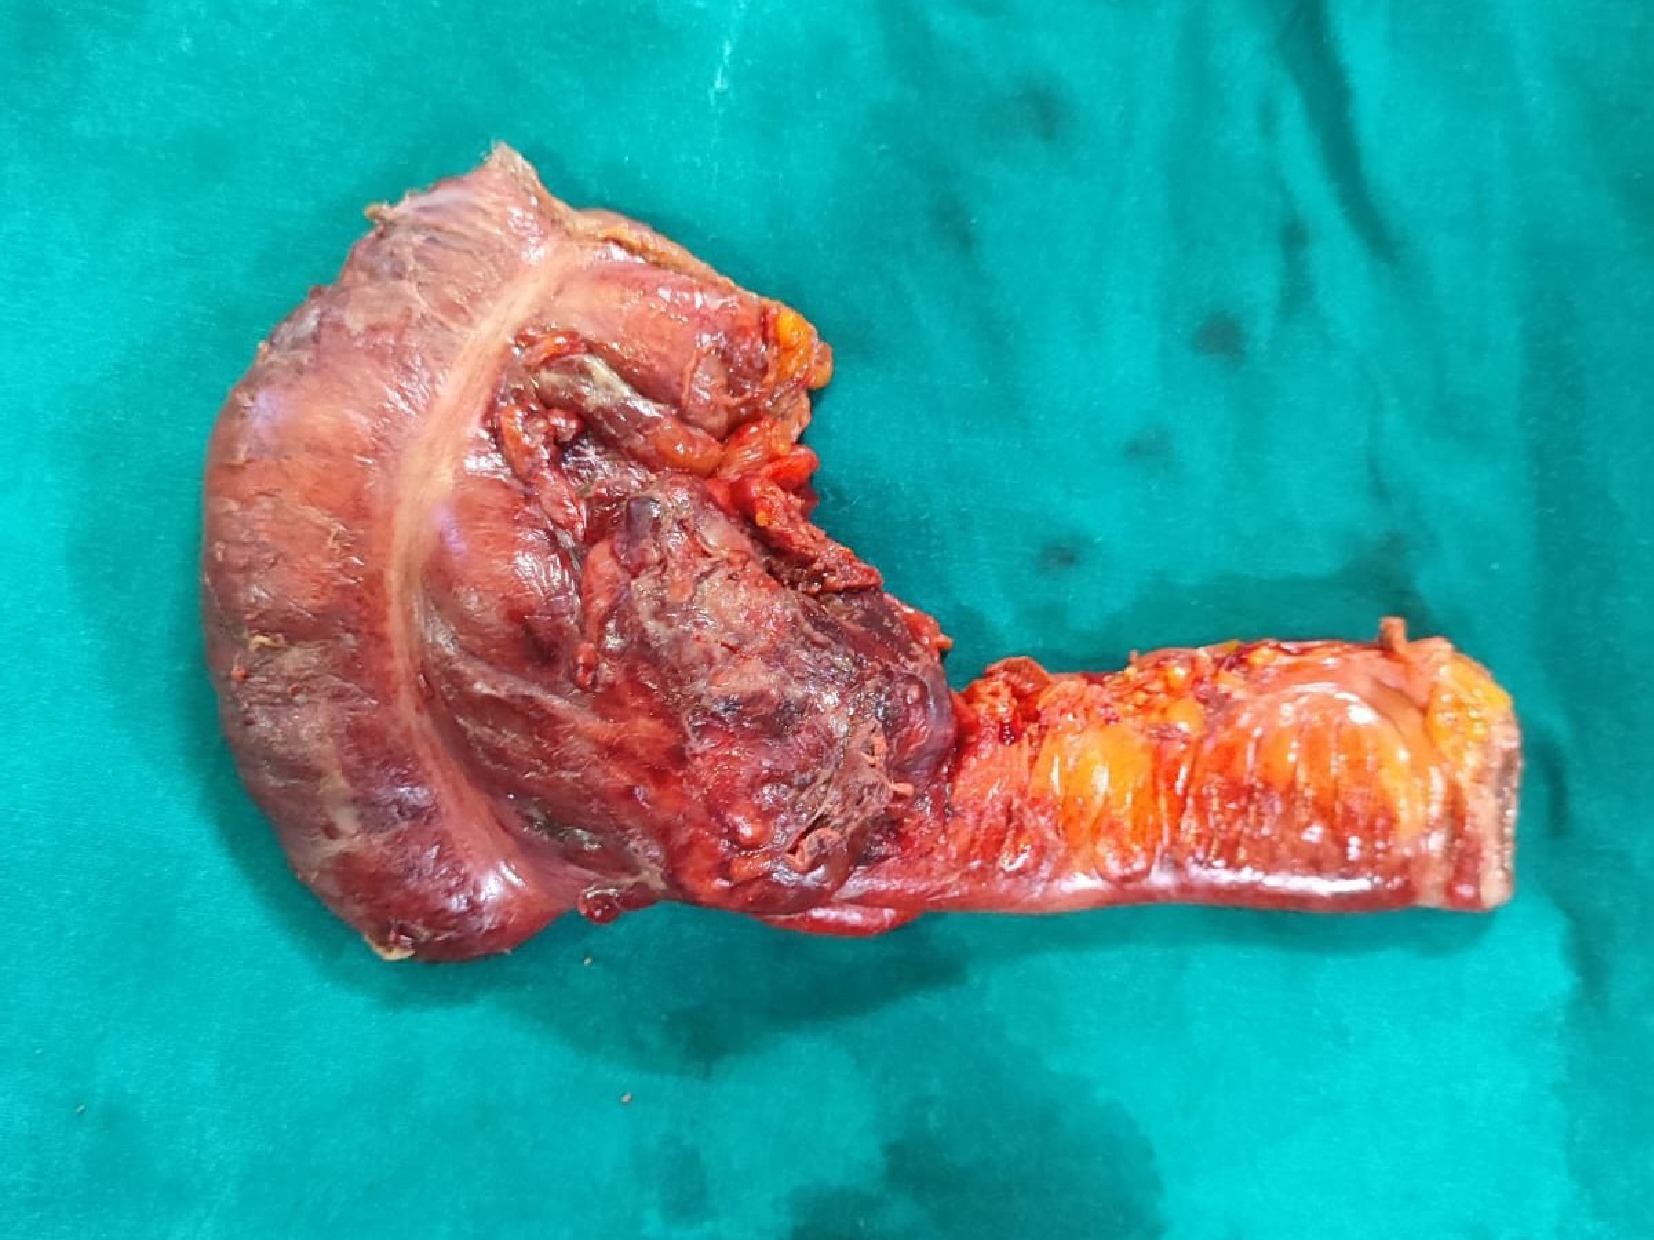

Due to worsening sepsis, the patient had exploratory laparotomy under vasopressor support. Around 300 ml of frank purulent material was drained and the omentum was found adherent to the small bowel loops, ascending colon, and the parietal wall. A hard mobile 7 × 5 mass was found at the ileo-caecal junction involving the caecal wall with serosal involvement and ulceration (Fig. 3). A limited right hemicolectomy was performed removing 9 cm of the distal ileum and 10 cm of the right colon. A hard 2 × 2 cm lymph node was found fixed to the right common iliac artery. An end ileostomy with a distal mucus fistula was created. The patient was extubated on the first post-operative day and discharged on day 7 uneventfully.

Figure 3.

Emergency limited right hemicolectomy specimen showing the growth involving the ileo-caecal junction.